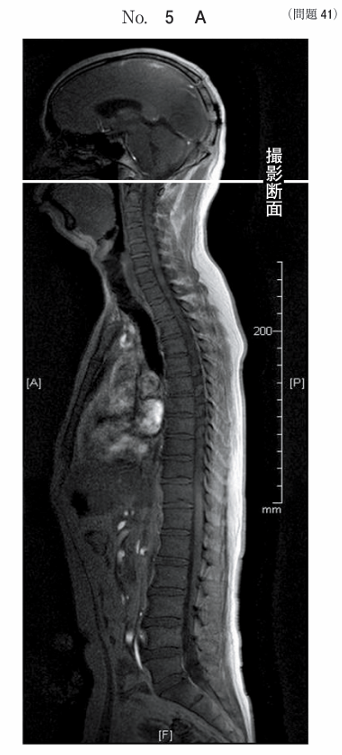

午前/問題41

脊椎のMR像別冊No. 5Aを別に示す。位置決め像の断面で得られる画像別冊No. 5Bはどれか。

1.ア

2.イ

3.ウ

4.エ

5.オ